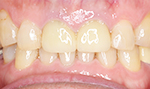

症例2

患者さんは60代男性 以前入れた保険の歯が色が変わって歯ぐきもやせたので白くしたいと希望術後

きれいに入って「こんなに保険の歯と違うのですか、入れて良かった」と喜んでおられました。

1本80000円(税別)

術前

術後